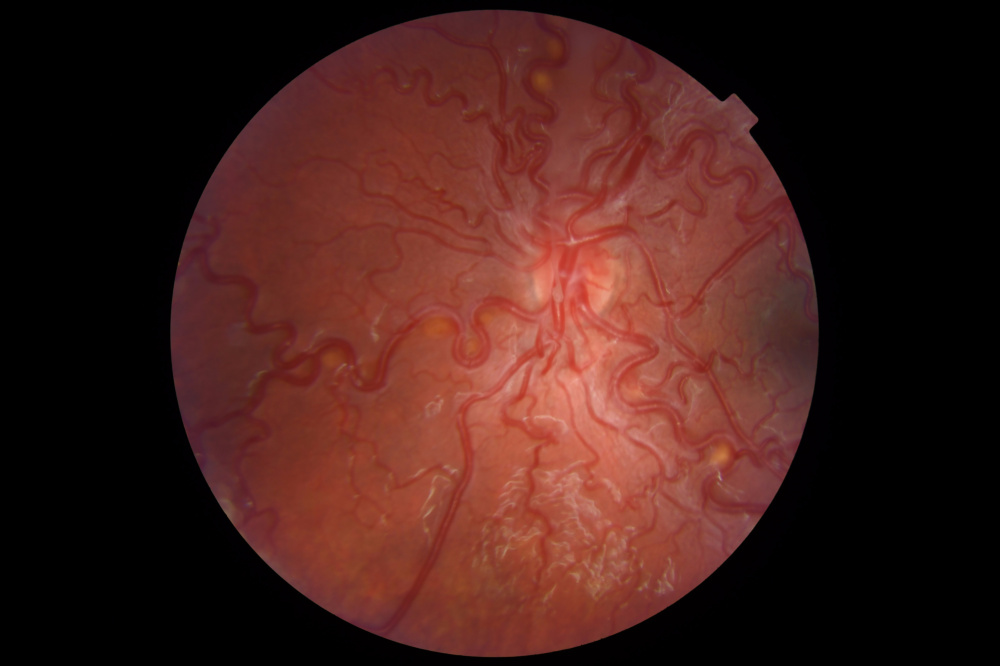

Título: The Serpent Crown of the Optic Disc

Autor: David Rosário Alves

Coautores: Sofia Oliveira Machado, Renato Santo Silva

Instituição: ULS São João, Centro Hospitalar Universitário de São João

Descrição: This photograph reveals tortuous vessels radiating from the optic disc, forming a striking serpiginous configuration reminiscent of the mythical crown worn by Medusa in Greek mythology. The image was obtained in a 13-year-old girl with unremarkable medical history, born at term, referred for routine pediatric ophthalmology evaluation. Ophthalmic examination revealed mild myopia, with best-corrected visual acuity of 1.0 in both eyes and no abnormalities on biomicroscopy. Fundoscopy of the left ey